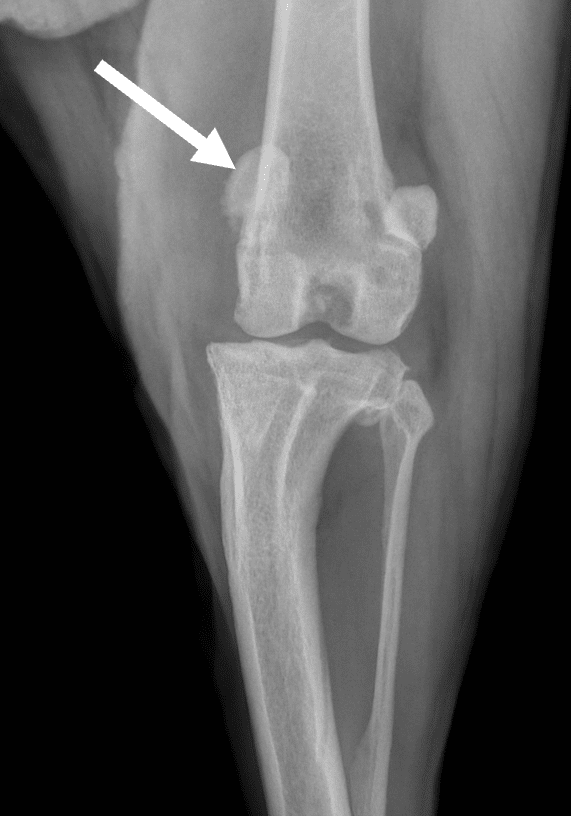

Des radiographies (et parfois même un scanner) peuvent également être réalisées dans le but :

– D’évaluer le degré d’arthrose

– De mettre en évidence d’éventuelles malformations osseuses associées

– D’exclure d’autres maladies pouvant se manifester par les mêmes symptômes

– De prévoir une chirurgie

Parfois, c’est une conformation anormale de la hanche, une malformation du fémur ou du tibia, ou une déviation de la crête tibiale qui peuvent être à l’origine d’une luxation de la rotule. Enfin, la trochlée dans laquelle glisse la rotule manque souvent de profondeur pour accueillir et maintenir la rotule en position.